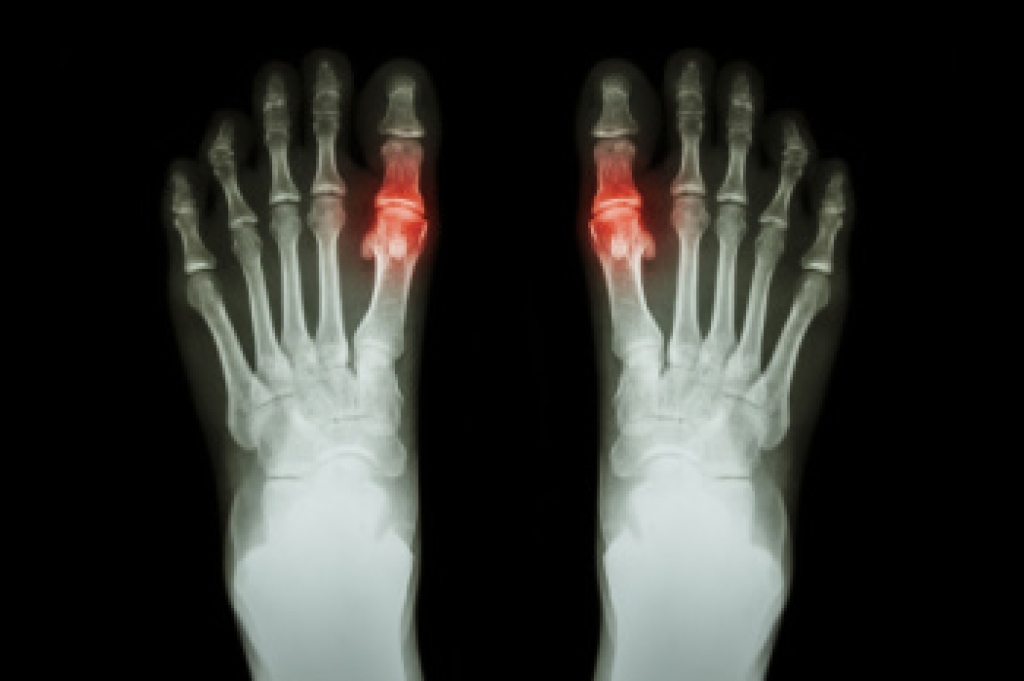

Seniors are enthusiastically embracing the pickleball trend, drawn to its social appeal and low-impact fitness benefits. While the game offers a fun way to stay active, it is important for older players to take steps to prevent injuries and achieve their fitness goals safely. Proper warm-ups and cool-downs are essential, as they prepare muscles and joints for the quick movements pickleball requires. Investing in supportive, well-fitting footwear with good grip can reduce the risk of slips and strain. Additionally, regular foot care, such as keeping toenails trimmed and managing conditions like bunions or corns, can enhance comfort and mobility on the court. Strengthening exercises for the ankles and feet can also build stability and reduce the chance of falls. Seniors who play pickleball can enjoy its benefits while staying safe. For any injuries, such as foot pain or fractures, it is suggested that you see a podiatrist for expert care.

Common Conditions

- Neuropathy – can reduce feeling in the feet and can hide many life-threatening medical conditions.

- Reduced flexibility – prevents the ability of proper toenail trimming, and foot cleaning. If left untreated, it may lead to further medical issues.

- Foot sores – amongst the older population can be serious before they are discovered. Some of the problematic conditions they may face are: